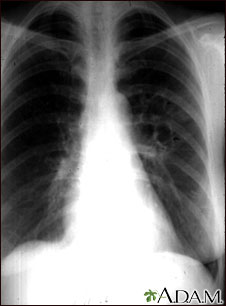

Your health care provider will perform a physical exam and ask about symptoms and travel history. Tests done for milder forms of this infection include:

- Blood test to check for antibodies to Coccidioides (the fungus that causes Valley fever)

- Chest x-ray

- Sputum culture

- Sputum smear (KOH test)